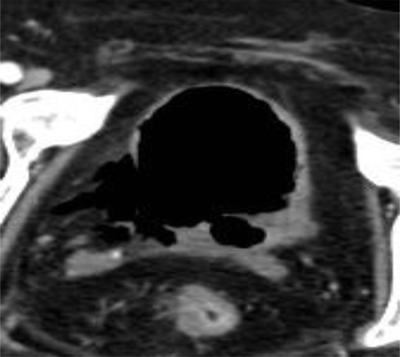

Figure 1

Axial unenhanced CT scan of the abdomen shows a disruption of the bladder wall at the right posterolateral side.